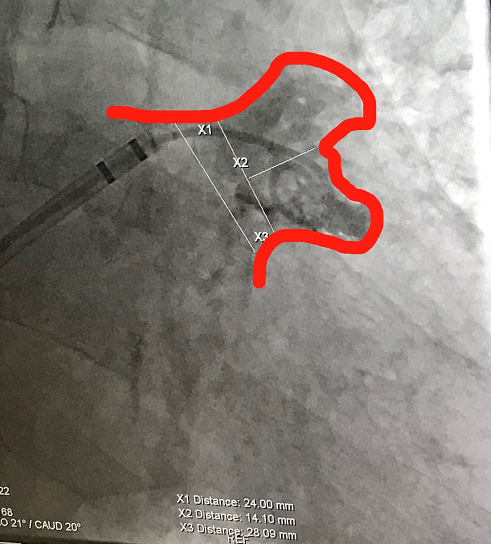

患者为71岁男性,心慌胸闷3年,加重伴头晕10个月。冷冻消融术后心房颤动,高血压,II型糖尿病,脑梗死。经食道超声测量显示患者心耳为双叶型,心耳特别浅。

(图:术前造影)

林逸贤教授选用型号为LT-LAA-1832,独特“小伞大盘”设计的LAmbre™左心耳封堵器置入其中一个叶内进行封堵。

手术过程非常顺利,术后造影显示,病人心耳封堵完全,无残余分流。